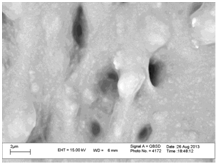

Test results of electron microscope (SEM)

The clonidine loaded CMS–1,4-PBD PMPs were characterized by FESEM for their size and distribution. Data showed that PMPs have a solid and near consistent structure. These PMPs have good spherical geometry. Figure 1 shows a representative SEM image of clonidine PMPs. Also, the results show that the surface of CMS–1,4-PBD PMPs shrank and a densely cross-linked gel structure was formed. The retardation of drug release from matrices of higher crosslinker content. The average drug entrapment was found to be 92.18±0.10%in the PMPs. The size of CMS–1,4-PBD PMPs was estimated by scanning electron microscopy (SEM) of the dried PMPs dispersions. The determination of PMPs size by SEM under a dry state does not result in an accurate absolute value of the hydrated PMPs size in dispersion, but only visualizes size range and particle shape. The incorporation of clonidine into the CMS–1,4-PBD PMPs produced a smooth surface and compact structure. The CMS–1,4-PBD PMPs are hydrophilic and would be expected to swell in water, thus producing a large hydro-dynamic size when measured by the Zetasizer. The particle size of PMPs is measured.

• Figure 1 Morphology of clonidine loaded CMS–1,4-PBD polymer-matrix 180 nanoparticle by emission scanning electron microscopy field